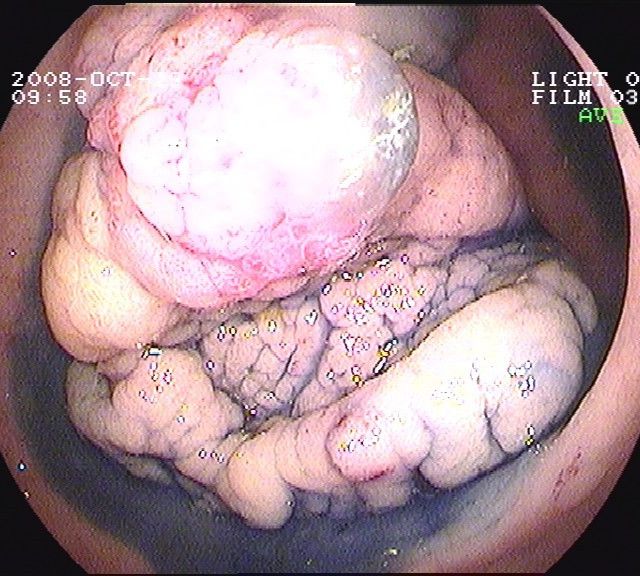

Coloskopie - riesiger rasenförmiger Polyp